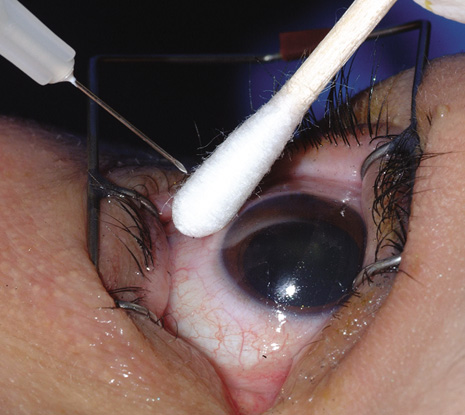

Endophthalmitis after intravitreal injection (Fig. 16) is an uncommon complication that has become the focus of attention in recent years as the use of intravitreal triamcinolone acetonide and various anti-angiogenesis medications have become available (Table 2). It is important to distinguish infectious endophthalmitis from a noninfectious pseudohypopyon caused by triamcinolone acetonide crystals (Fig. 17). Another modality, pneumatic retinopexy, is also rarely associated with the development of endophthalmitis. In the multicenter clinical trial on pneumatic retinopexy, one patient out of 103 eyes in the pneumatic retinopexy group developed endophthalmitis. A total of three endophthalmitis cases have now been reported following pneumatic retinopexy.115–117 The most common isolate is S. epidermidis and treatment approaches include standard intravitreal antibiotic injection as performed in postsurgical endophthalmitis. Strategies to reduce the risk of endophthalmitis include using a povidone-iodine ocular preparation (Fig. 18), using a lid speculum (Fig. 19), and avoiding needle contact with the lid margins and lashes (Fig. 20).

Fig. 18. A povidone-iodine preparation is used to prepare the eye for an intravitreal injection.

Fig. 19. A lid speculum maintains the lid position and allows access to the pars plana region for intravitreal injection.

Fig. 20. In spite of the preparation with povidone-iodine, it is recommended that needle contact with the lid margins and lashes be avoided.